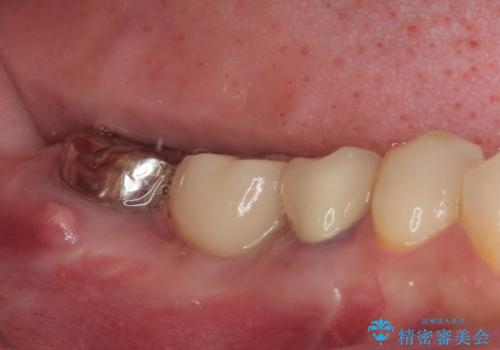

放置していたむし歯 抜歯即時埋入インプラントによる補綴治療

- むし歯を放置したままで、インプラント治療を希望して来院された患者様です。

左右ともにインプラントが必要な状態でした。

左下小臼歯は根管治療で対応する予定でしたが、診断のために歯肉を開いたところ頬側に垂直破折が認められたため、抜歯即時埋入インプラントによる補綴治療を選択することとしました。

右下は大臼歯部の歯は抜歯即時埋入インプラントにて、手前の歯は保存して補綴治療を行うこととしました。

インプラント埋入時に十分な安定値を得ることができたため、速やかに仮歯を装着し、最小限の通院回数で治療を終えることができました。